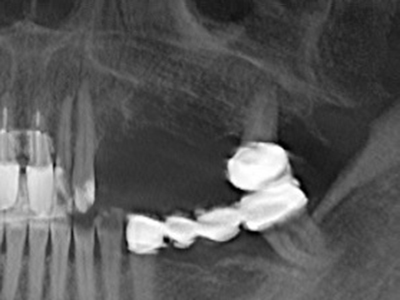

La preparación de la ventana lateral en la elevación del suelo del seno maxilar representa un enorme reto, sobre todo para profesionales de la implantalogía que tienen poca experiencia en técnicas quirúrgicas. Retirar la cobertura ósea del seno maxilar sin provocar daños en la membrana de Schneider es tan solo una parte de la operación; tras crear un acceso suficiente, es preciso movilizar con cuidado la mucosa del seno maxilar a fin de dejar espacio para el material o los implantes que vayan a incorporarse. En esta aplicación la cirugía piezoeléctrica resulta útil en dos sentidos: por un lado, el uso de insertos diamantados permite realizar una retirada selectiva del hueso y, si se actúa con cuidado, la membrana permanece intacta, y por otro lado, las frecuencias de ultrasonidos favorecen también un desprendimiento sin problemas de la membrana, pues se transfieren al espacio comprendido entre la mucosa y el suelo del seno maxilar gracias al uso de piezas romas especiales (Cassetta, Ricci et al. 2012, Pereira, Gealh et al. 2014) (Rickert, Vissink et al. 2013). De este modo, no es de extrañar los trabajos publicados en la actualidad sobre la técnica de elevación del suelo del seno maxilar mediante la técnica de Caldwell-Luc con instrumentos piezoeléctricos (Wallace, Tarnow et al. 2012).